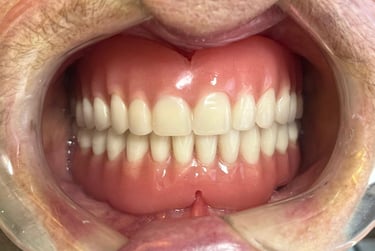

Prótese total convencional

Depois

Solução tradicional e econômica para quem perdeu todos os dentes. Embora a prótese protocolo sobre implantes ofereça mais estabilidade, a prótese total continua sendo uma alternativa acessível que devolve função e estética ao sorriso.

Antes